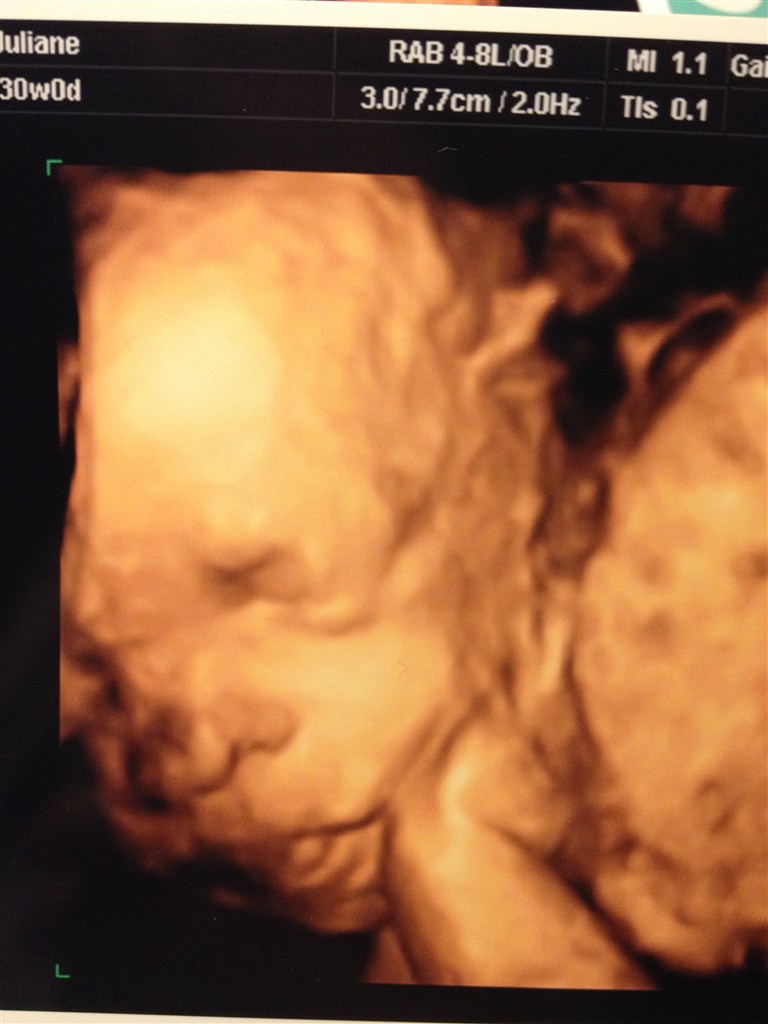

Og vil da lige vise indholdet, af maven.. Vi var nemlig til 3d scanning i Onsdags, fantastisk oplevelse..